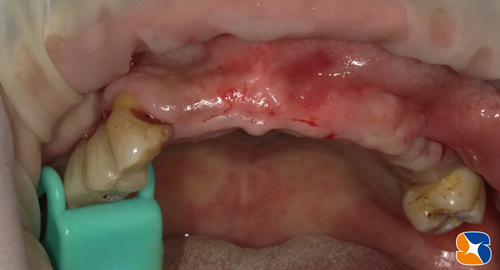

(3)患者様のアゴ骨の一部を採取したものに、β-TCP(動物由来の骨でない人工骨)とCGF(特定細胞加工物フィブリンゲル)を混合させて骨の欠落部を埋めます。

最後、CGF(フィブリンゲル)を圧接した膜を何層にも重ねて、切開した歯肉を元通りに閉じます。